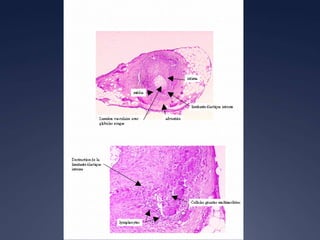

Périartérite noueuse

 Biopsie

 Inflammation périvasculaire

 Nécrose fibrinoïde de la média

 Atteinte de l’endothelium

 Puis fibrose…

 Musculaire permet diagnostic dans 60 %

 Rénale déconseillée

 Cutanée

 Vasculiteleucocytoclasiquenon-spécifique